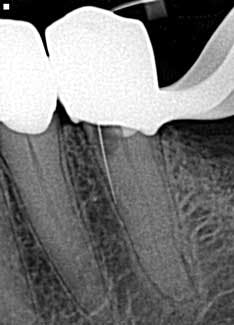

• File separation

Spin, spin, and snap! This is my least favorite endodontic complication (figure 3), which is why I wrote an entire article on it.